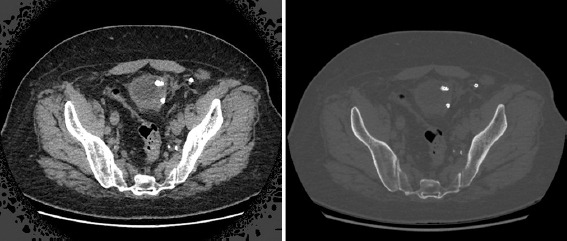

Background: Migration of fixing tacks into the bladder wall is a rare complication following laparoscopic hernia repairs.

Case presentation: This report detailed an 80-year-old male who presented to the clinic with hematuria. Cystoscopy revealed a bladder calculus adherent to the bladder wall, with an underlying metallic tack. A stent snare was used to secure the edges of the tack, and a resectoscope loop was carefully used to resect and free it from surrounding mucosa.

Conclusion: This was the first case report to describe the successful removal of a metallic fixing tack from the bladder through a transurethral approach in a patient post-hernia repair.